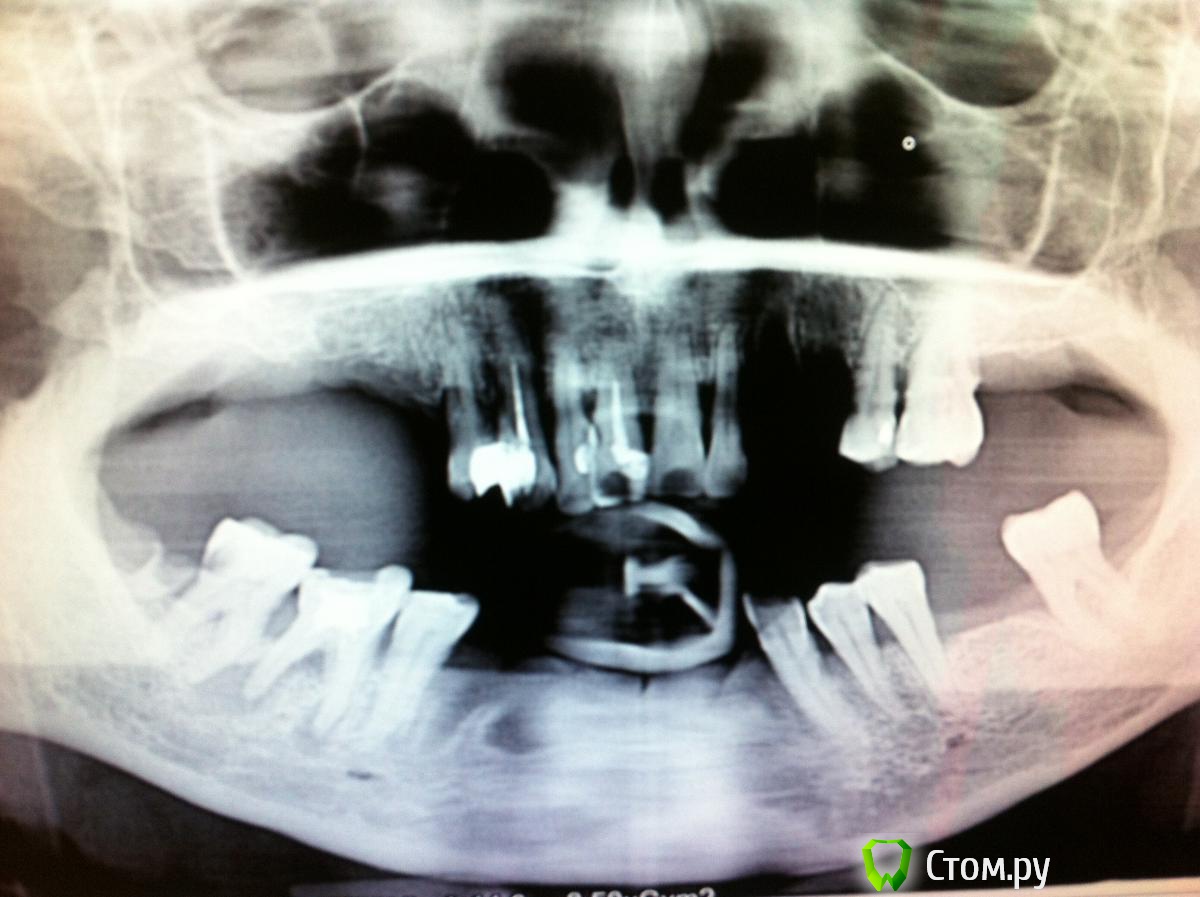

ksenistom Опубликовано 14 апреля, 2014 Поделиться Опубликовано 14 апреля, 2014 Здравствуйте, будьте добры выскажите свое мнение по составлению плана лечения?!К сожалению фото полости рта у меня нет, ПАЦИЕНТ ХОЧЕТ ВОССТАНОВИТЬ ФУНКЦИЮ ЖЕВАНИЯ И ПО ВОЗМОЖНОСТИ эстетики при небольшом бюджете, т.е. от имплантации отказался!Зубы верхней челюсти 1ст. подвижности, нижней неподвижны...прилагаю ОПТГ: Ссылка на комментарий